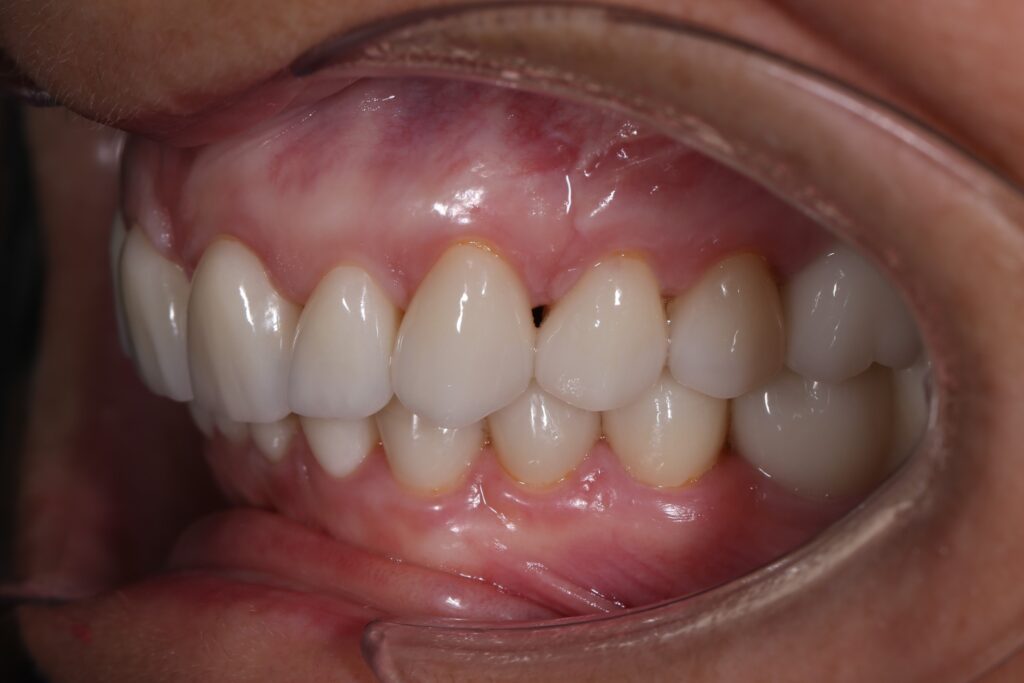

Ситуация до лечения

Из-за множественных давних удалений жевательных зубов, произошла деформация зубных рядов, зубы разъехались в область удаленных, что затрудняло протезирование в момент обращения к ортопеду.

Так же можно отметить сильное снижение высоты прикуса (верхние зубы на 100% перекрывали нижние, что вызывало хроническую травму десны), а также повышенную стираемость твердых тканей зубов, что является следствием повышенной нагрузки, которую много лет испытывали передние зубы, в связи с отсутствием жевательных зубов.